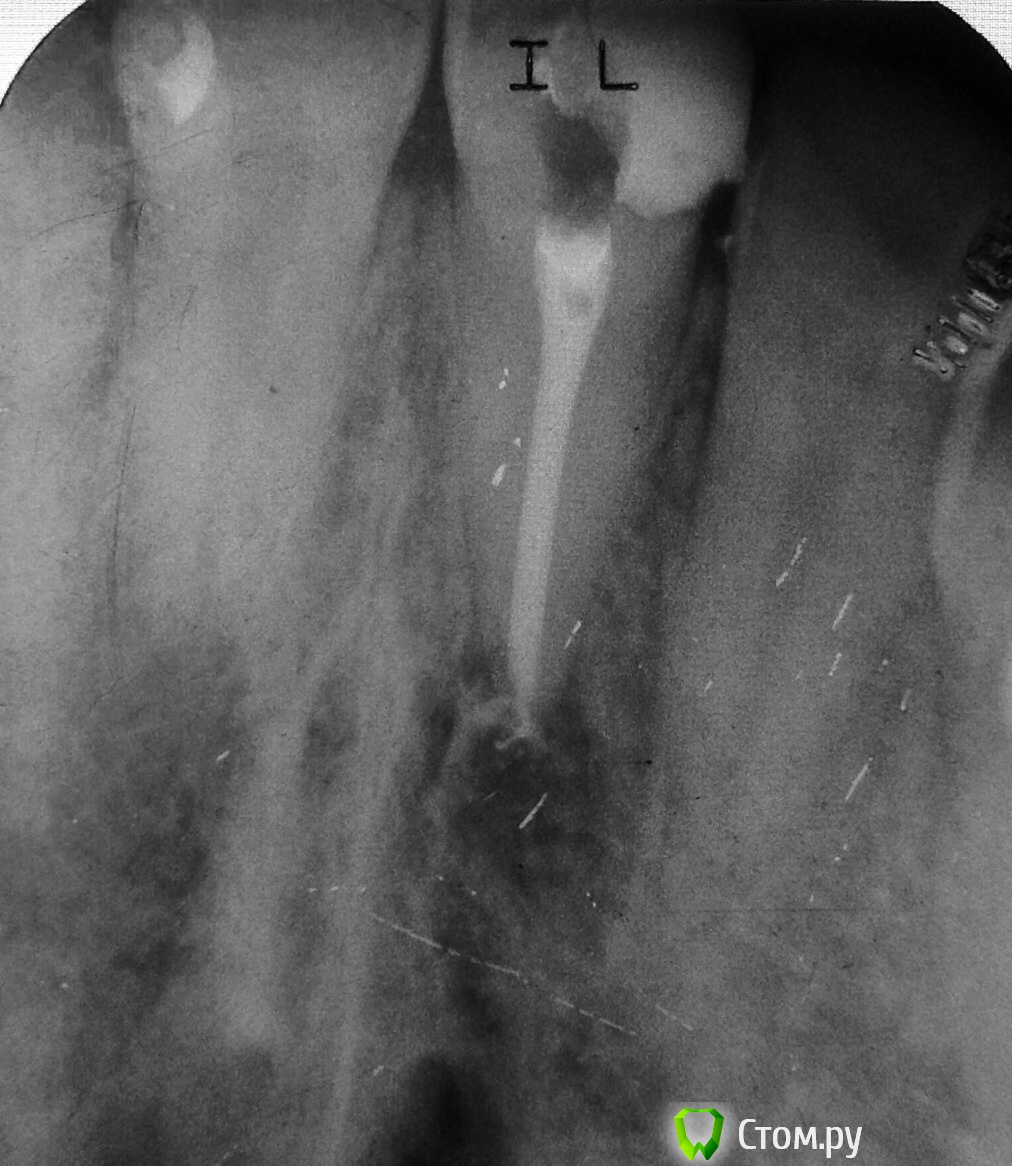

AMaPbI4 Опубликовано 30 ноября, 2013 Поделиться Опубликовано 30 ноября, 2013 Здравствуйте) 2 недели назад обратился мужчина, 39 лет, по острой боли, 11 зуб. Перкуссия и пальпация по переходной болезненна, на рентгене очаг. Композитрая реставрация с нарушенным краевым прилеганием. Делали год назад в поликлинике. Коффер, раскрылся и потекло) 55 файл слегка подклинился в апексе, до него все вылетали со свистом. Долго мыл, сформировал упор 70 файлом, почесал стенки хедструмом, высушить полностью не удалось. UltraCal в подтекающий канал, НПВС, отпустил. Резать не стал. На следующий день к вечеру клиника начала стихать. Во второе посещение вымыл кальций, помылся, высушил. За 5-7 минут экспозиции пина в канале, кончик остался абсолютно сухим. Залатералил. Реставрация в то же посещение. Теперь собственно вопрос, который не дает мне спать: учитывая время полной полимеризации AH+ И исходный размер апекса, может стоило апикально закрыть МТА? Все таки 5 минут ни разу не показатель сухости в канале. Ссылка на комментарий

Marina_A Опубликовано 30 ноября, 2013 Поделиться Опубликовано 30 ноября, 2013 (изменено) Теперь собственно вопрос, который не дает мне спать: учитывая время полной полимеризации AH+ И исходный размер апекса, может стоило апикально закрыть МТА? Все таки 5 минут ни разу не показатель сухости в канале.да, большие апексы лучше закрывать МТА.а какая рабочая длина была? Изменено 30 ноября, 2013 пользователем Marina Antoniuk Ссылка на комментарий

ger_berra Опубликовано 30 ноября, 2013 Поделиться Опубликовано 30 ноября, 2013 Если нет симптомов,то в данной ситуации остается только ждать реколл.А так да,лучше МТА закрывать. Ссылка на комментарий

Ico Опубликовано 30 ноября, 2013 Поделиться Опубликовано 30 ноября, 2013 Все будет хорошо,красивое эндо! Ссылка на комментарий